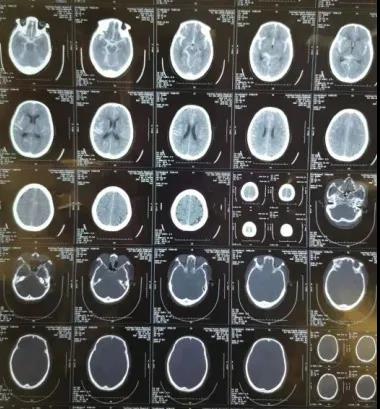

近日,我院神经外科二病区成功完成一例动脉瘤介入栓塞术。

一直以来,我院在诊疗自发性蛛网膜下腔出血方面,经验少,手段有限,患者不得不转外院治疗,以至于给患者造成巨大经济负担。自2018年神经外科二病区顺利开展了颅内动脉瘤开颅夹闭手术后,为诊治“自发性蛛网膜下腔出血伴颅内动脉瘤破裂”行开颅夹闭积累了一定经验。2019年底,我院安装了GE大型数字剪影血管造影机,主任康宏达带领科室医师积极开展新业务,新技术,目前可通过神经介入动脉瘤栓塞治疗颅内动脉瘤,为自发性蛛网膜下腔出血患者提供了另一种治疗选择。